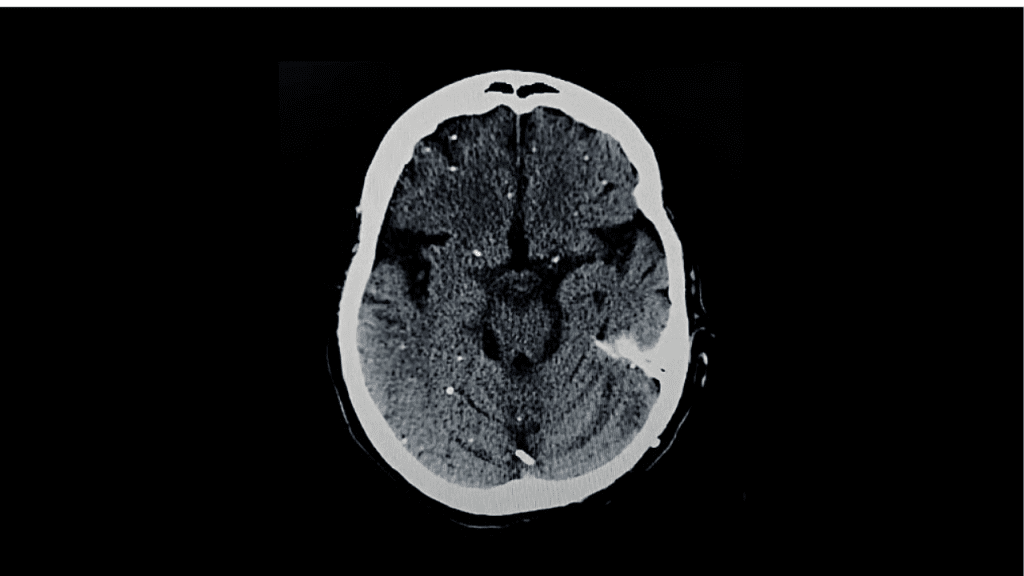

En la mayoría de las personas sanas, la infección no produce síntomas evidentes. Tras la fase inicial, el parásito forma quistes tisulares en órganos como el cerebro, los músculos y el corazón. Durante años, estos quistes se consideraron estructuras completamente inactivas.

Sin embargo, el estudio publicado en Nature Communications en 2026 demostró que esta idea era incompleta. Los investigadores hallaron que los quistes no son homogéneos, sino que albergan diversos subtipos del parásito, cada uno con funciones y comportamientos distintos.

La toxoplasmosis suele ser leve, pero puede causar complicaciones graves en personas con sistemas inmunológicos debilitados, como pacientes trasplantados o con VIH. También representa un riesgo durante el embarazo, debido a posibles daños al feto.

Los tratamientos actuales se enfocan principalmente en las formas activas del parásito y tienen dificultades para eliminar los quistes. El nuevo estudio sugiere que esta limitación existe porque los fármacos no consideran la diversidad interna de los quistes.

Al identificar qué subtipos tienen mayor probabilidad de reactivarse, los científicos abren la puerta a terapias más precisas, capaces de atacar el núcleo real de la infección. Esto podría mejorar significativamente la eficacia de futuros medicamentos.

La evidencia científica confirma que Toxoplasma gondii no permanece completamente dormido dentro del cerebro. Sus quistes son estructuras activas y complejas, lo que transforma nuestra comprensión de la toxoplasmosis y del parásito, y marca un paso clave hacia tratamientos más efectivos.